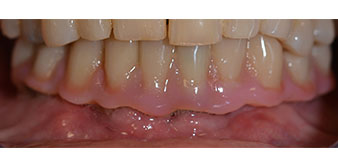

The 64-year-old patient presented with residual dentition of teeth 38, 33 and 43 and a clasp denture in the mandible (Fig. 1 and 2).

Fig. 1

Fig. 2